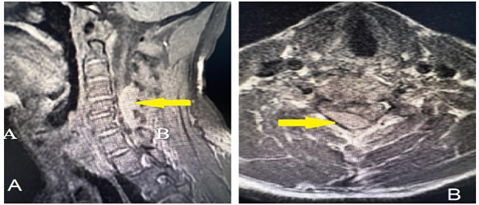

An MRI of the cervical spine with contrast revealed cervical spine extradural compression extending from the C4-C6 level, a hypointense signal on the T1-weighted image, a hyperintense signal on T2-weighted imaging, and no contrast enhancement. There was significant compression of the thecal sac and spinal cord on the right side, extending along the exiting nerve root into the neural foramina evident at the C6 level, as shown in Figure 1.

Figure 1: Preoperative MRI of cervical spine T2-weighted image with a hypertense signal in sagittal (A) and axial (B) cuts showing an extradural compression extending from the C4-C6 level as indicated by the yellow arrow.